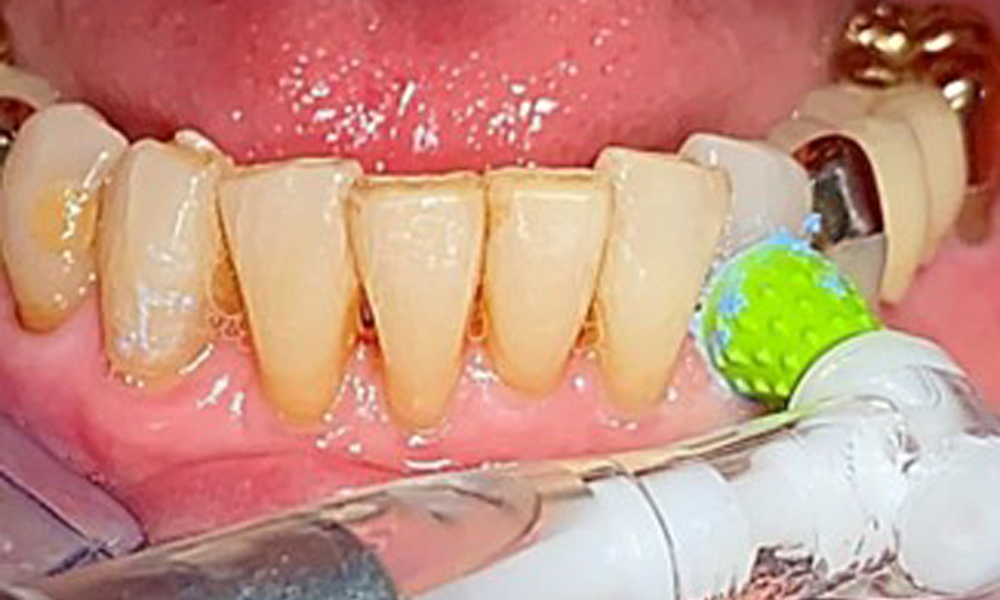

An air polishing system should be used with low-abrasive powder to remove biofilm from the restoration margins, interdental areas and implant surfaces (Fig. 12). Selective polishing (Fig. 13) should be used to smooth any less sensitive areas, as this decreases bacterial reattachment (9).